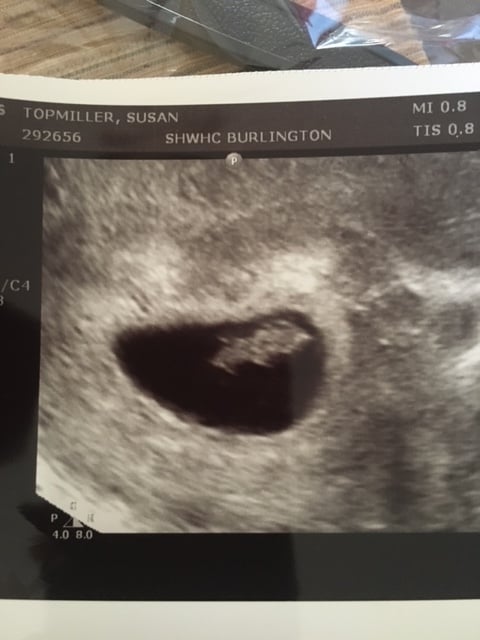

Sorry it's enormous but I suck at computers. I'm measuring exactly 8 weeks today and heart rate was 166. It was so nice to know that all the nausea and boob pain is not all in my head. There's a real person in there!